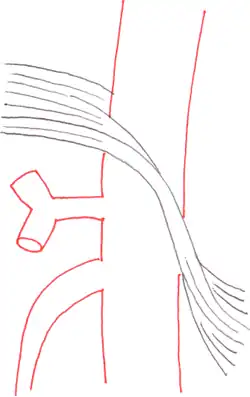

По мнению исследователей, формирование КСЧС связано с особенностями строения и развития аортального отверстия диафрагмы. Аортальное отверстие диафрагмы образуется сухожильными краями правой и левой ножек диафрагмы, соединяющей их срединной дугообразной связкой диафрагмы и телами позвонков. В норме у здорового человека срединная дугообразная связка диафрагмы (СДСД) расположена непосредственно над устьем чревного ствола. Однако у некоторых людей СДСД расположена ниже устья чревного ствола, что приводит к сдавлению сосуда и, как следствие, нарушению в нём кровообращения. На ангиографических снимках таких пациентов можно видеть, как чревный ствол придавлен к брюшной аорте, сужен вблизи своего устья и патологически расширен ниже места сдавления.

Наиболее информативным методом диагностики КСЧС является ангиография сосудов брюшной полости. Сущность метода состоит в том, что в артерию пациента вводится контрастное вещество, которое заполняет сосуд и, блокируя рентгеновское излучение, отображается на рентгеновских снимках. Это позволяет получить рентгенографические изображения чревного ствола и определить наличие и степень его сужения. Разновидностью ангиографии является компьютерно-томографическая ангиография, при которой контрастное вещество вводится в вену. Этот малоинвазивный метод исследования позволяет получить чёткие трёхмерные изображения брюшной аорты и её ответвлений. При экстравазальной компрессии чревного ствола на ангиографических снимках видно, как сосуд сдавлен у основания и прижат к брюшной аорте[1]. В боковой проекции чревный ствол искривлён и изогнут кверху, а по его верхнему краю определяется вдавление. Нижняя стенка сосуда не деформирована, а дистальнее стеноза определяется постстенотическое расширение[5]. Иногда ангиография позволяет визуализировать сдавливающую сосуд серповидную связку или ножку диафрагмы.